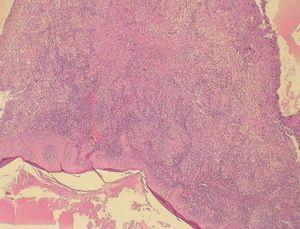

El resultado de la biopsia mostró un denso infiltrado inflamatorio en dermis superficial y profunda, acompañado de numerosos cuerpos ovalados de unas 6 micras, tanto dentro como fuera de los macrófagos, que se corresponden con los amastigotes (forma intracelular que adopta la Leishmania en el huésped, a diferencia de la forma promastigote que adopta en el mosquito vector) (figs. 3 y 4).

Figura 3.

Figura 4.